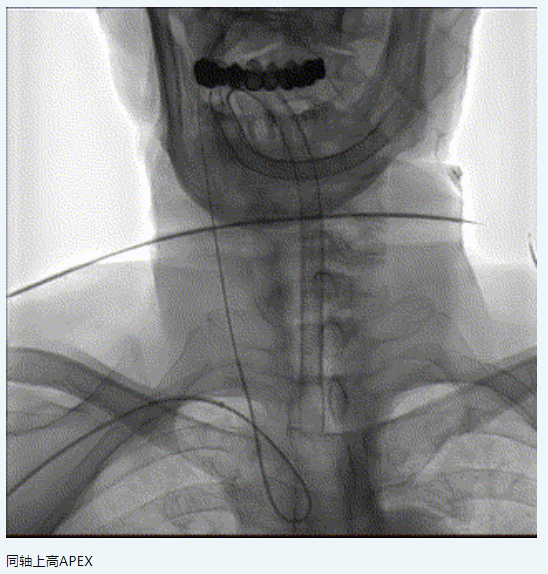

【伙伴喜訊】應用APEX 081橈系統(tǒng)經(jīng)橈行Neuro LPS低壓球囊聯(lián)合NOVA顱內(nèi)藥物洗脫支架治療頸內(nèi)動脈C6段狹窄

主訴:男,78歲,左側偏癱,言語含糊1月。

現(xiàn)病史:患者1月前因“左側偏癱,言語含糊”就診我科,溶栓后僅留有言語含糊(NIHSS評分1分)出院,出院診斷為“腦梗死,右側頸內(nèi)動脈C6段重度狹窄,高血壓病3級極高?!?,此次為進一步處理血管回診我科。

二、術前影像

橈動脈系統(tǒng):APEX TRA SYSTEM 7F-105cm+140cm-SIM2

6.7F APEX TRA SYSTEM橈系統(tǒng):1、外徑細(2.32mm),對橈動脈侵擾小,內(nèi)腔大(0.081”):可兼容5F中間導管高到位;經(jīng)橈專用,弓部支撐性較長鞘、導引導管、中間導管、DA更強;APEX橈系統(tǒng)配套有130/140cm長SIM2,長SIM2管同軸治療可避免交換失敗,使顱內(nèi)病變更加便捷。